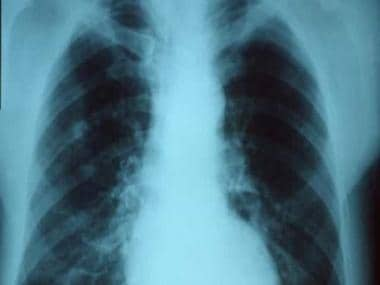

Pneumonia infection. Image courtesy CDC Public Health Image Library/Wikimedia Commons

In Pneumonia, a person’s lung tissue gets affected along with the air sacs of the lungs. Inflammation can also lead to water or pus in the alveoli and lung tissue, thereby causing difficulty in breathing, leading to death. Pneumonia affects people of all ages, with children and adults being more at risk. An individual can have mild to acute Pneumonia, depending on how severe the inflammation is.